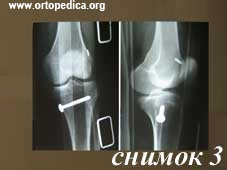

3. Рентгенограмма после операции